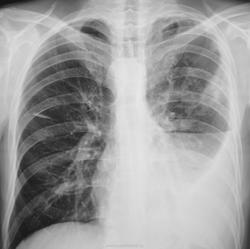

Через год плановое исследование.